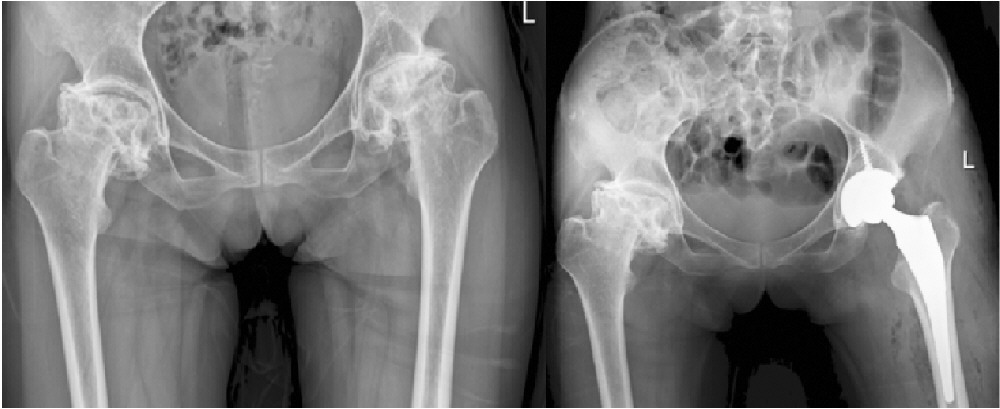

到医院检查时,结果令人揪心:张大姐的股骨头已完全塌陷,原本光滑的球状结构扭曲变形,关节间隙几乎消失。这彻底击碎了保守治疗的希望。在辗转多家医院、尝试各种方法无果后,几乎绝望的张大姐抱着最后一丝希望,找到了暨南大学附属第一医院的张还添教授。

考虑到张大姐病情复杂、股骨头变形严重,团队决定采用机器人辅助手术。术前,机器人系统根据她的三维CT数据,精准规划了假体型号、植入位置与角度。术中,机械臂作为“超级助手”,精准完成了骨骼打磨与假体安放。医生术中发现,张大姐的股骨头已严重变形、色泽暗沉,形如干瘪的“旧式粽子”,病损程度远超预期。在机器人的辅助下,病变股骨头被顺利移除,适配的人工关节被稳妥植入,髋关节的力学结构与旋转中心得以完美重建。